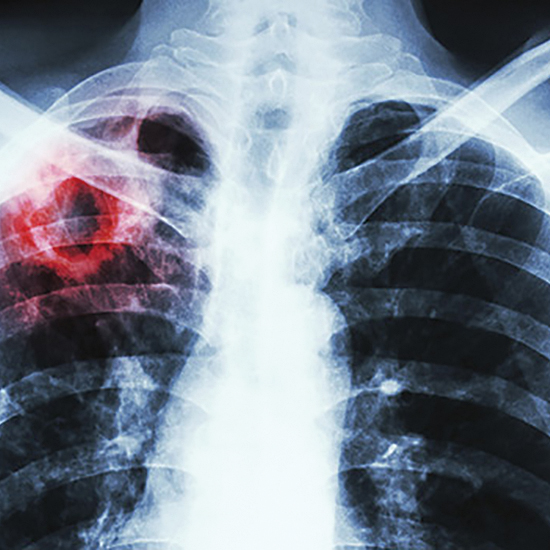

За інформацією Мартіна ван ден Бума, експерта Європейського Бюро ВООЗ, у 2016 р. в Європі захворіли 290 тис. осіб: з них 32 тис. дітей, 87 тис. жінок. Померли від туберкульозу 26 тис. хворих на туберкульоз, з них 4 800 дітей. Як зазначив експерт, на фоні зменшення кількості випадків туберкульозу та смертності від нього в Європі зростає кількість випадків мультирезистентного туберкульозу, ко-інфекції туберкульоз/ВІЛ та смертність ко-інфекції туберкульоз/ВІЛ. Кожен п’ятий випадок туберкульозу в Європі — мультирезистентний туберкульоз, а кожен восьмий — туберкульоз, поєднаний із ВІЛ-інфекцією.

У своїх виступах фахівці підкреслили, що ситуація з туберкульозом в Європі загалом контрольована. Крім того, спостерігається загальна тенденція до зниження захворюваності на туберкульоз в Європі. Зокрема, за даними 2015 р., у Чехії захворюваність становила 4,9 на 100 тис. населення, в Австрії — 7,3; в Угорщині — 8,0, у Польщі — 17,0. У 2017 р. у Словаччині виявлено 249 випадків туберкульозу. Для таких країн, як Словаччина, Словенія, Угорщина, Польща, Австрія, Чехія, актуальною проблемою є висока захворюваність серед ромського населення, у тому числі серед дітей ромської національності.

За словами Юрія Варченка, головного фахівця з профілактики та нагляду за туберкульозом відділу координації програм лікування туберкульозу Центру громадського здоров’я МОЗ України, який представляв Україну: «Порівняно із країнами Європейського Союзу в нашій державі висока захворюваність серед населення. Є свідчення про недостатню ефективність лікування та пізню діагностику туберкульозу в Україні. Проте також існує стійка тенденція до зниження захворюваності на туберкульоз, покращення ефективності лікування як чутливого, так і резистентного туберкульозу, — сказав Ю. Варченко. — Зараз у державі впроваджуються нові режими лікування, закуповуються нові протитуберкульозні препарати та відбувається покращення діагностики туберкульозу».

У ході дискусії пріоритетними викликами в боротьбі з туберкульозом, актуальними для країн Європейського Союзу, експерти визначили профілактику, виявлення і лікування латентної туберкульозної інфекції, туберкульоз таких ключових груп, як ромське населення, мігранти, соціально дезадаптовані особи, особи з коморбідністю ВІЛ-гепатит-цукровий діабет і туберкульоз у дітей.